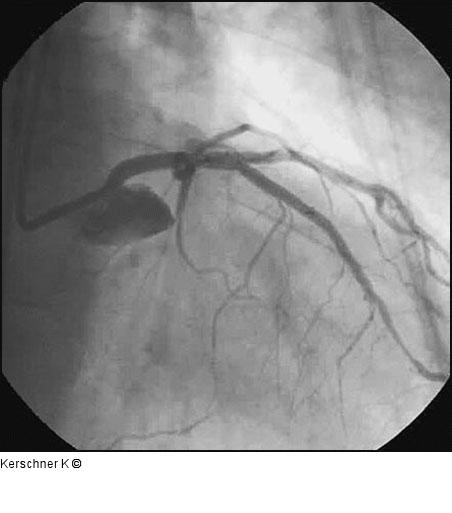

Kerschner K Patient mit Ostiumstenose-Hauptstamm und Bifurkationsstenose - R. interventricularis anterior / R. diagonalis Journal für Kardiologie - Austrian Journal of Cardiology 2005; 12 (9-10): 252 Volltext (PDF) Fallbeschreibung Übersicht

Abbildung 12: Endergebnis RAO/kranial |